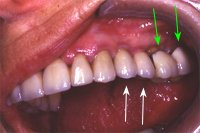

Ein 31 Jahre alter Patient zeigt einen starke Zahnfleisch-Rückgang im Oberkiefer (Abb. 1 und 3) und wir beschliessen, diese Rezessionen zu behandeln.

Der Erfolg der Behandlung ist deutlich in den Abb. 2 und 4 zu sehen. Sehr augenfällig konnte die Situation um den Eckzahn im linken Oberkiefer verbessert werden (vergleiche dazu Abb. 3 vorher und Abb. 4 nachher).